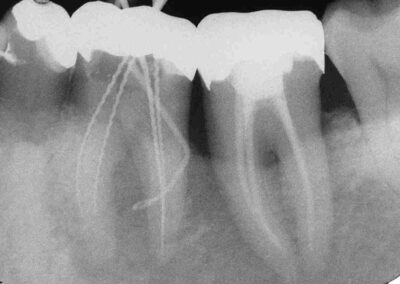

Unmittelbar nach WF im April 2007 bei Beschwerdefreiheit und geschlossener Fistel (Klick!)

1. Verlaufskontrolle im August 2007 bei anhaltender Beschwerdefreiheit und unauffälligem Sondierungsbefund (Klick!)